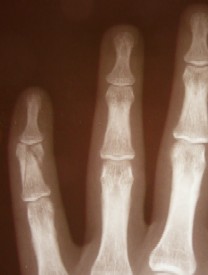

Photographer: Nevit Dilmen

Fracture of the Middle Phalanx of

The Pinky Finger

However, there are a some non-limb fractures discussed by period surgeons. You may recall the case William Clowes discusses concerning a fractured rib. Clowes did not set the bone, rather he simply put medicine and bandages on it.1 Richard Wiseman discusses a case where he repairs a fractured collar bone, although all he has to say about restoring the bone is that it was "set and bound up, with resolution not to open it till it should be united."2

While hands and feet are technically parts of the limbs, they contain many small bones in great density, so they are treated separately in period medical books. With regard to fingers, John Atkins says that "the straightening of a Finger is the replacing of it; if any Particle of Bone is an Obstruction to this, or separated, it is to be removed; and if the Wound be so large as to shew the Bone, it should be covered with dry Lint, or a Dossil [roll of lint] pressed out of Tinct. Myrrh.[a cleansing and healing medicine]."3